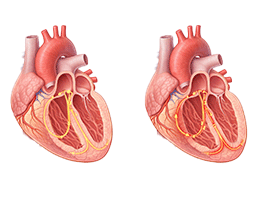

심근경색 (Myocardial Infarction)

협심증 (Angina Pectoris)

심근병증 (Cardiomyopathy)

심장판막질환 (Valvular Heart Disease)

심부전 (Heart Failure)

비대성심근병증 (Hypertrophic Cardiomyopathy)

확장성심근병증 (Dilated Cardiomyopathy)

울혈성심부전 (Congestive Heart Failure)

심근염 (Myocarditis)

심막염 (Pericarditis)

심내막염 (Endocarditis)

심장판막질환 (Heart Valve Disease)

확장형심근병증 (Dilated cardiomyopathy)

비후성심근병증 (Hypertrophic cardiomyopathy)

제한성심근병증 (Restrictive cardiomyopathy)